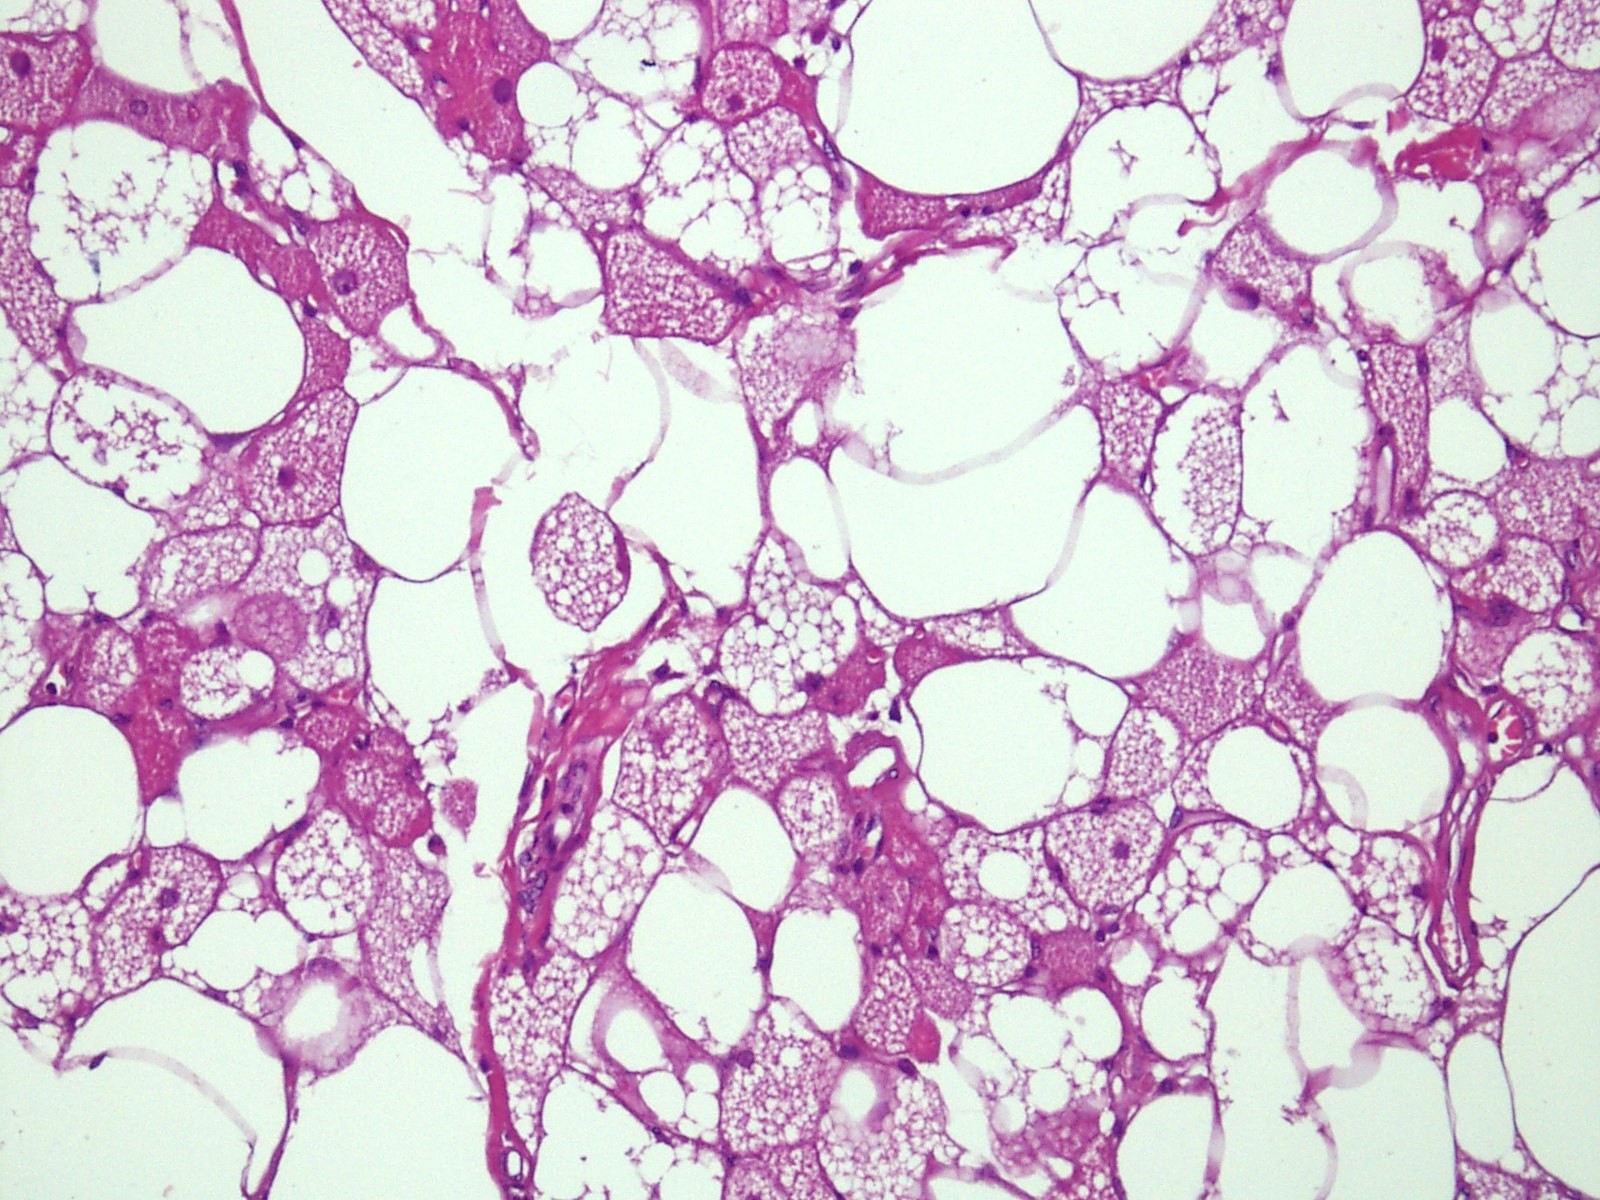

Microscopic (histologic) description

- Neoplastic lesion composed of polygonal brown fat cells with stromal cells in the background (Case Rep Oncol 2017;10:438)

- Large number of pale and eosinophilic brown fat cells with multivacuolated, eosinophilic granular cytoplasm and small central nucleus (about 70%) admixed with variable amount of univacuolated white cells (Case Rep Oncol 2017;10:438, Am J Case Rep 2020;21:e921447, J Comput Assist Tomogr 2019;43:793, J Pathol Transl Med 2017;51:499, Am J Surg Pathol 2018;42:951, Virchows Arch 2021;478:527)

- Multivacuolations resemble lipoblasts

- Morphological variations or subtypes: typical, myxoid (9%), lipoma-like (7%), spindle cell (2%), thick bundles of collagen fibers, presence of mast cells and exclusively containing brown fat cells (Case Rep Oncol 2017;10:438, Am J Case Rep 2020;21:e921447, Virchows Arch 2021;478:527)

- Cytological atypia, necrosis and mitosis is unusual (J Pathol Transl Med 2017;51:499, Am J Surg Pathol 2018;42:951, BMC Surg 2021;21:30)

Microscopic (histologic) images